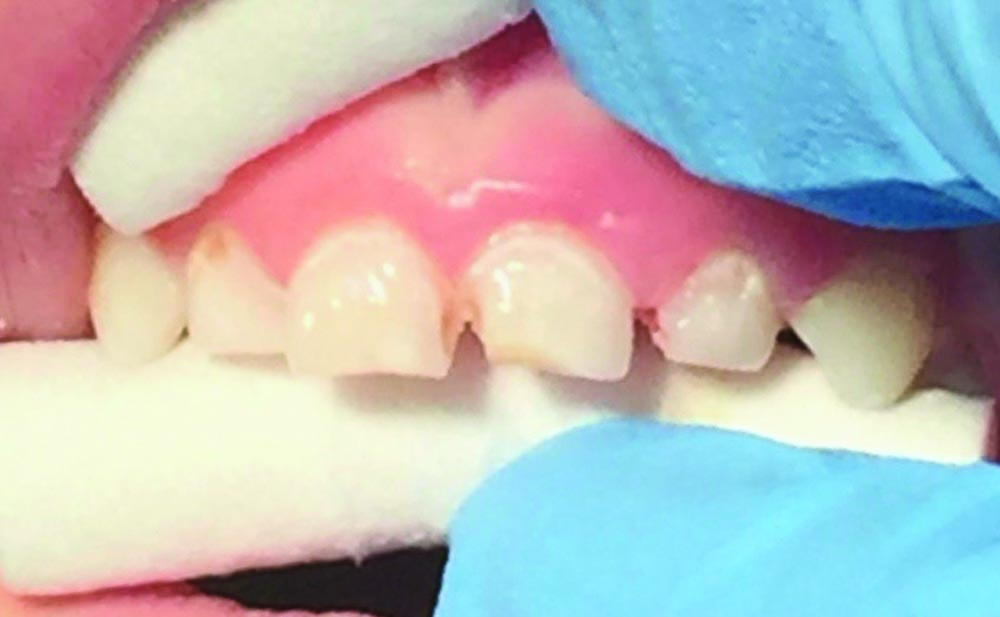

Caries was excavated with a spoon excavator (Fig. 7). Because isolation was a challenge, all surfaces of affected teeth were bonded with a self-etch procedure using Futurabond U and then light-cured (Fig. 8). Celluloid strip crowns were fitted and vented, filled with GrandioSO by Voco, seated and light-cured.

Celluloid strips were removed and composite strip crowns were polished with Enhance polishing cups by Dentsply. Final restorations are functional and aesthetic (Fig. 9). Because of the process of minimally invasive technique and adaptable materials, it was possible to carry out this procedure in office without local anesthetic, resulting in a successful restorative outcome and a positive patient experience.